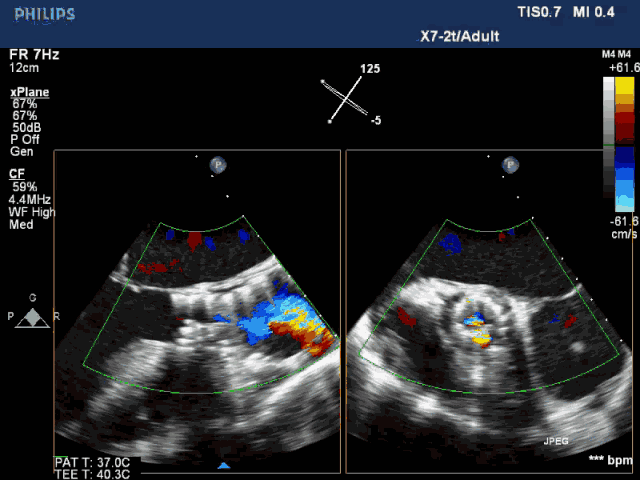

释放后造影见中度瓣周漏,彩超提示支架没有充分打开

复查彩超,瓣膜贴壁良好,无瓣周漏,残余压差<10mmHg

术后即刻LVEF 35.4%,较术前显著改善